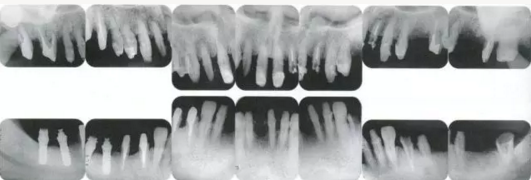

【牙位異?!垦牢划惓r的牙周外科處理-接觸點異常(一).png

▲圖15-1,2

在正畸??漆t(yī)生處接受了正畸治療,雖然上頜正畸治療已經(jīng)完成,但由于磨牙區(qū)的邊緣嵴不整齊而導(dǎo)致牙體之間存在空隙。要想在這個狀態(tài)下護理牙周組織以及咬合狀況是非常困難的。由此可見,在治療時,正畸專科醫(yī)生與全科口腔醫(yī)生保持目標一致是非常重要的。